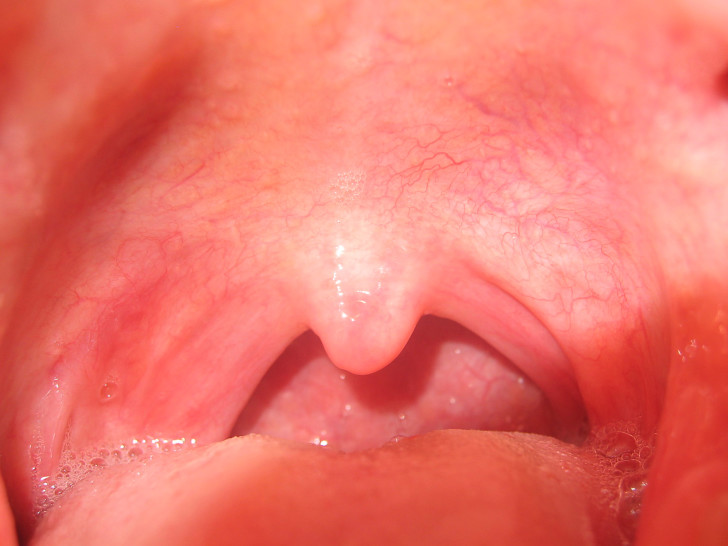

Термином “горло” принято называть видимую часть ротоглотки – именно по ее состоянию опытные родители пытаются понять, заболел ребенок или нет. Красное горло – крайне распространенный симптом, который нужно уметь правильно определять. Как должно выглядеть здоровое и больное горло, можно рассмотреть на фото. Остановимся на этом вопросе подробнее.

Отграничить больное горло от здорового не так сложно – во втором случае участок не имеет насыщенного красного оттенка, гланды не увеличены. Проблема в том, что в настоящее время встречается все больше детей с хроническими заболеваниями миндалин. Горло у здорового ребенка выглядит следующим образом:

- гланды имеют свело-розовый цвет;

- налет или воспаления отсутствуют;

- бугорки на здоровых миндалинах должны быть малозаметными и равномерными;

- все ткани около зева должны иметь один оттенок (светло-розовый);

- задняя стенка глотки не имеет пятен и по цвету схожа с остальными тканями.

Врачи отмечают, что здоровое горло у ребенка имеет светло-розовый цвет, а миндалины не увеличены и не воспалены. При осмотре горла можно увидеть ровные, гладкие стенки, без налетов и покраснений. В норме миндалины имеют небольшие размеры и не вызывают дискомфорта при глотании.

Здоровый человек имеет 4 миндалины: 2 парные и 2 непарные, располагаются они в месте перехода носоглотки в глотку. В норме эти образования имеют размер грецкого ореха, окрашены в светло-розовый цвет. Также к признакам нормальных миндалин относят:

- отсутствие покраснений и налета;

- слизистая оболочка не воспалена, нет ярко выраженного сосудистого рисунка;

- гланды не соприкасаются с небными дужками, не выходят за их пределы;

- при надавливании на миндалины медицинским шпателем не выделяется гной или слизь.

О здоровье человека говорит совокупность всех перечисленных признаков. Однако для некоторых людей увеличенный размер гланд является нормой – это индивидуальная особенность организма.